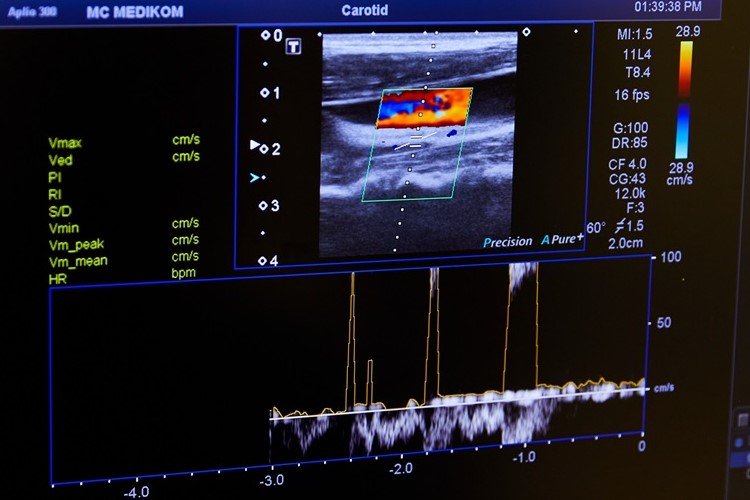

- Медицина: Доплерографія — метод, що використовує ультразвук для вивчення кровотоку. Вона здатна попередити про звуження артерій чи тромби.